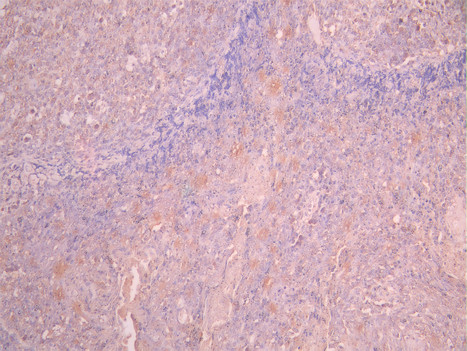

IHC image of CSB-RA957044A0HU diluted at 1:100 and staining in paraffin-embedded human cervical cancer performed on a Leica BondTM system. After dewaxing and hydration, antigen retrieval was mediated by high pressure in a citrate buffer (pH 6.0). Section was blocked with 10% normal goat serum 30min at RT. Then primary antibody (1% BSA) was incubated at 4°C overnight. The primary is detected by a Goat anti-rabbit polymer IgG labeled by HRP and visualized using 0.05% DAB.